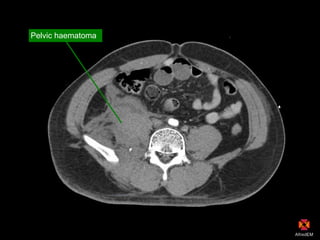

Pelvic haematoma

Rpt CT Abdo: progression pelvic haematoma

Blush = Arterial Bleed

Angio-embolisation

Theatre if fails